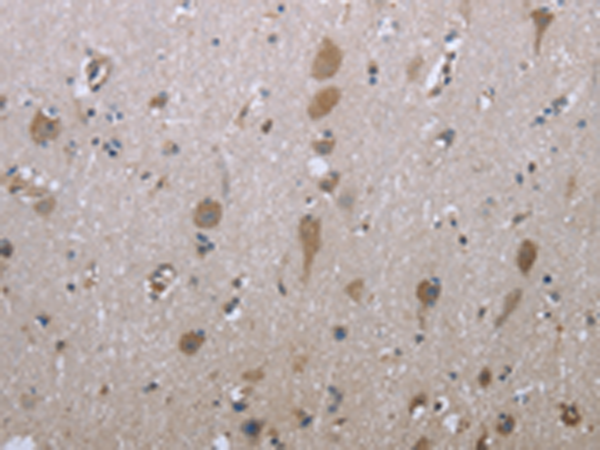

IHC positive control:

Human brain

IHC Recommend dilution:

50-100